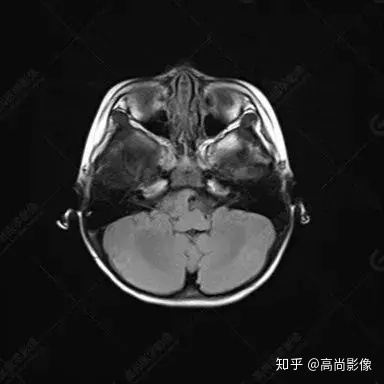

右側(cè)顳葉腫瘤切除術(shù)后(具體不詳):右側(cè)顳部骨質(zhì)不連續(xù)呈術(shù)后改變,右側(cè)顳葉術(shù)區(qū)見片狀長(zhǎng)T1長(zhǎng)T2信號(hào)影,F(xiàn)LAIR呈低信號(hào);術(shù)區(qū)后方右側(cè)顳枕葉見一巨大占位性病變影,邊界欠清,大小約6.2×5.8×4.3cm(前后×左右×上下),信號(hào)不均勻,T1WI呈等稍低信號(hào)間雜少許高信號(hào),T2WI呈高稍低混雜信號(hào),DWI示部分病灶彌散受限,相應(yīng)ADC圖減低,磁敏感序列見部分呈極低信號(hào),增強(qiáng)掃描可見明顯不均勻強(qiáng)化,鄰近硬腦膜及小腦幕增厚并明顯強(qiáng)化;另延髓右前方及右側(cè)橋小腦角區(qū)見一不規(guī)則形異常信號(hào)影,大小約3.2×1.3×3.7cm(左右×前后×上下),呈長(zhǎng)T1稍長(zhǎng)T2信號(hào),F(xiàn)LAIR呈等信號(hào),DWI未見受限,增強(qiáng)后明顯均勻強(qiáng)化,鄰近腦膜明顯強(qiáng)化。鄰近腦實(shí)質(zhì)及右側(cè)顳角明顯受壓;左側(cè)大腦半球未見局灶性信號(hào)異常,中線結(jié)構(gòu)稍左移。

右側(cè)顳葉腫瘤切除術(shù)后:現(xiàn)術(shù)區(qū)后方右側(cè)顳枕葉及延髓右前方占位,右側(cè)顳枕部硬腦膜及小腦幕明顯強(qiáng)化,結(jié)合既往影像資料,考慮為胚胎源性惡性腫瘤,如非典型畸胎樣/橫紋肌樣瘤(AT/RT)或原始神經(jīng)外胚層腫瘤(PNET)。

非典型畸胎樣/橫紋肌樣瘤(AT/RT) 是一種高度惡性中樞神經(jīng)系統(tǒng)腫瘤,臨床罕見,臨床表現(xiàn)無(wú)特異性,好發(fā)于 5 歲以下兒童,尤以 3 歲以下多見,在兒童原發(fā)性中樞神經(jīng)系統(tǒng)(CNS)腫瘤中占 1%~3%。該腫瘤體積一般較大,幕上大于幕下,有明顯的占位效應(yīng)。該腫瘤成分復(fù)雜,囊變、出血、壞死常見。因此 AT/RT信號(hào)混雜,囊性部分呈 T1WI低、T2WI高信號(hào),增強(qiáng)后不強(qiáng)化;若瘤體出血,囊內(nèi)可見T1WI稍高信號(hào)、T2WI低信號(hào),實(shí)性部分在 T1WI上呈混雜等、低信號(hào),在T2WI 及 T2-FLAIR上呈混雜等高信號(hào),增強(qiáng)掃描后大部分呈環(huán)形條帶樣明顯強(qiáng)化,中心壞死區(qū)不強(qiáng)化。另外,該腫瘤實(shí)性成分在DWI上呈高信號(hào),說(shuō)明腫瘤細(xì)胞核密集,水分子擴(kuò)散明顯受限,提示該腫瘤惡性程度高,容易復(fù)發(fā)及轉(zhuǎn)移。